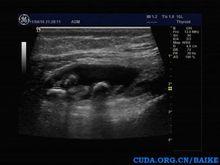

膝關節髕上囊積液伴遊離體形成病理及組織學診斷

病理學肉眼觀,滑膜局限或廣泛受累,瘤體大小不一,數目不等,呈灰白色半透明小體,直徑從1mm-3mm不等。單發的巨大結節稱為巨大孤立性滑膜軟骨瘤,也可見到。原發的滑膜軟骨瘤病關節表面正常,繼發者關節表面常有退行性變。組織學上,瘤體可鈣化或骨化;滑膜內出現軟骨性結節,排列欠整齊,軟骨細胞數目量多,體積大,具有多形性體積較大的胞核,細胞表現有異型性,但是本病為良性的非侵襲性疾病。

Milgraml將滑膜骨軟骨瘤病分為三期:I期為活動性(軟骨化生,無小體);II期為過渡期(化生,有小體);III期為靜止期(有小體無化生)。